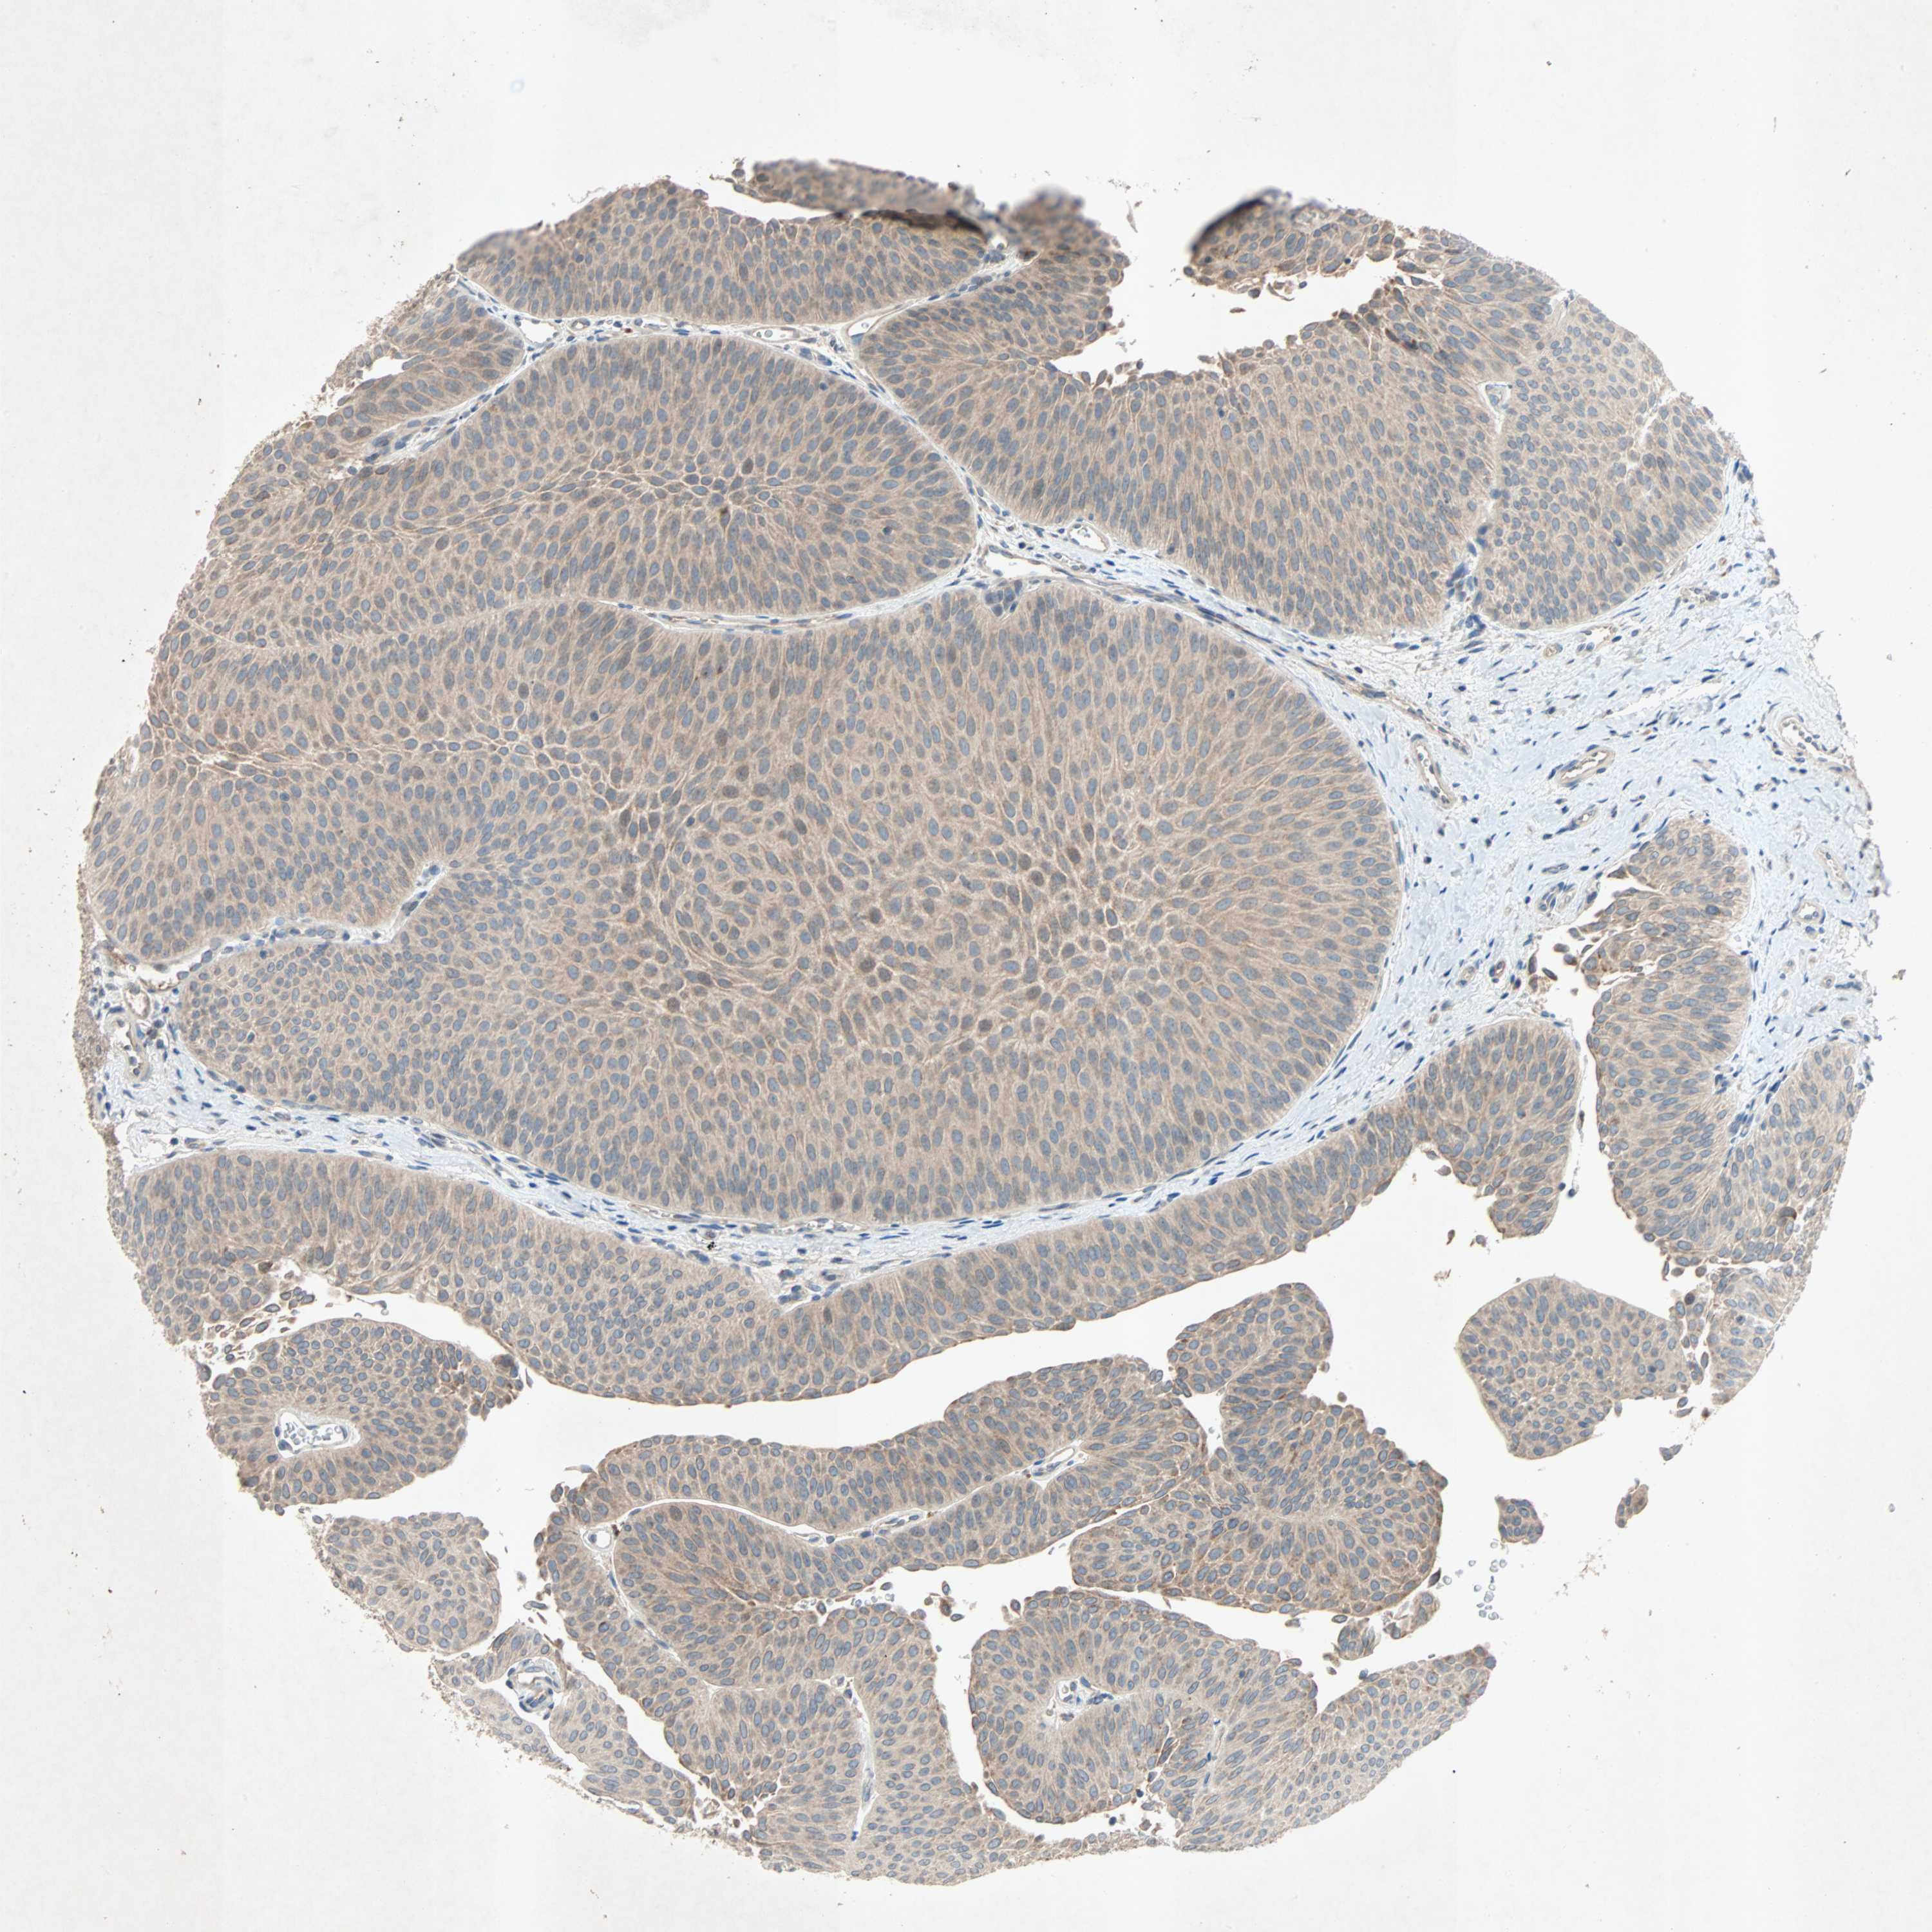

UROTHELIAL CANCER - Protein expressioni

A mouse-over function shows sample information and annotation data. Click on an image to view it in a full screen mode. Samples can be filtered based on level of antibody staining by selecting one or several of the following categories: high, medium, low and not detected. The assay and annotation is described here.

Note that samples used for immunohistochemistry by the Human Protein Atlas do not correspond to samples in the TCGA dataset.

Antibody stainingi

Antibody staining in the annotated cell types in the current human tissue is reported as not detected, low, medium, or high, based on conventional immunohistochemistry profiling in selected tissues. This score is based on the combination of the staining intensity and fraction of stained cells.

Each image is clickable and will lead to virtual microscopy that enables deeper exploration of all samples and also displays staining intensity scores, fraction scores and subcellular localization as well as patient and tissue information for each sample.

Antibody HPA007478

Antibody HPA007966

Urothelial carcinoma, Low grade

Urothelial carcinoma, High grade